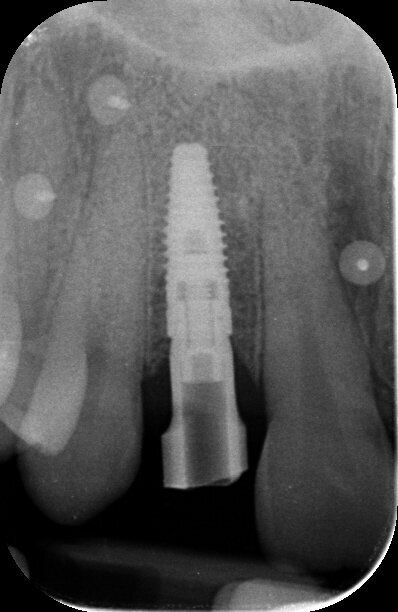

Fig. 14 - Rx endorale dello scan body in posizione.

Le successive fasi protesiche provvisorie consistono nel modellare la regione cervicale della corona al fine di ottenere un condizionamento dei tessuti molli che ottengano, durante la maturazione, una festonatura simile a quella dell’elemento omologo controlaterale e un buon mimetismo radicolare in visione laterale. Giunti a questo punto della terapia, la paziente richiede anche la correzione della recidiva ortodontica che caratterizza gli incisivi centrali superiori, valutando il riallineamento dell’elemento dentario 1.1 che risulta mesioverso e lievemente sovrastante il versante mesiale dell’elemento 2.1. Dopo uno studio ortodontico del caso, si propone una terapia ortodontica con degli allineatori trasparenti che, in pochi mesi, corregge il mal posizionamento dentario soddisfacendo le richieste estetiche della paziente. Valutata clinicamente e radiograficamente la salute e la stabilità dei tessuti duri e molli fino a questo punto trattati (Fig. 13), si procede con le fasi di protesizzazione definitiva. L’impronta definitiva è rilevata seguendo il protocollo digitale e utilizzando lo scanner intraorale Trios 3Shape (Figg. 14, 15).

La tecnologia digitale permette di diminuire il disagio intraoperatorio, di accorciare i tempi operatori e di aiutarci nella rilevazione del colore degli elementi dentari contigui all’elemento da ripristinare, dettaglio di primaria importanza durante il trattamento di un caso ad alta valenza estetica come quello descritto. La prova estetica e il controllo radiografico sono fasi protesiche inevitabili perché ci permettono di indagare la corretta interfaccia tra l’impianto e la corona e di garantire che le aspettative estetiche della paziente vengano soddisfatte. La consegna della corona definitiva eseguita in metallo ceramica avviene serrando la vite protesica con un torque control dinamometrico tarato ad un valore di 35 N/cm2; il controllo in posizione di relazione centrica, del tragitto percorso durante i movimenti protrusivi e di lateralità permette di escludere la presenza di precontratti che potrebbero rivelarsi deleteri per la sopravvivenza nel lungo periodo del manufatto protesico.